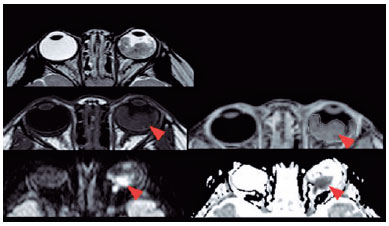

MRI demonstrated a 100% accuracy in retinoblastoma diagnosis. Moreover, some subcentimeter lesions (<0.5 cm) were found only in the sequence balance in our protocol (Figure 3).